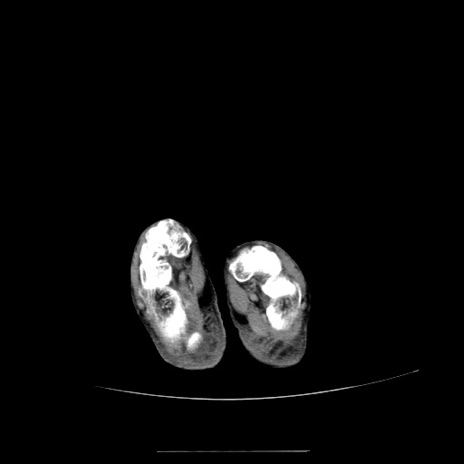

冠状断像

【症例】70歳代女性

【主訴】お腹が張る

【現病歴】1週間くらい前から腹部膨満の自覚あり。昨日夜から増悪したため、本日救急外来受診。

【身体所見】意識清明、BT 36.5℃、BP 165/106mmHg、HR 80bpm、SpO2 98%、腹部:膨満、軟、自発痛・圧痛なし、触診にて不快感あり、腸蠕動音:減弱

【データ】WBC 12600、CRP 1.04